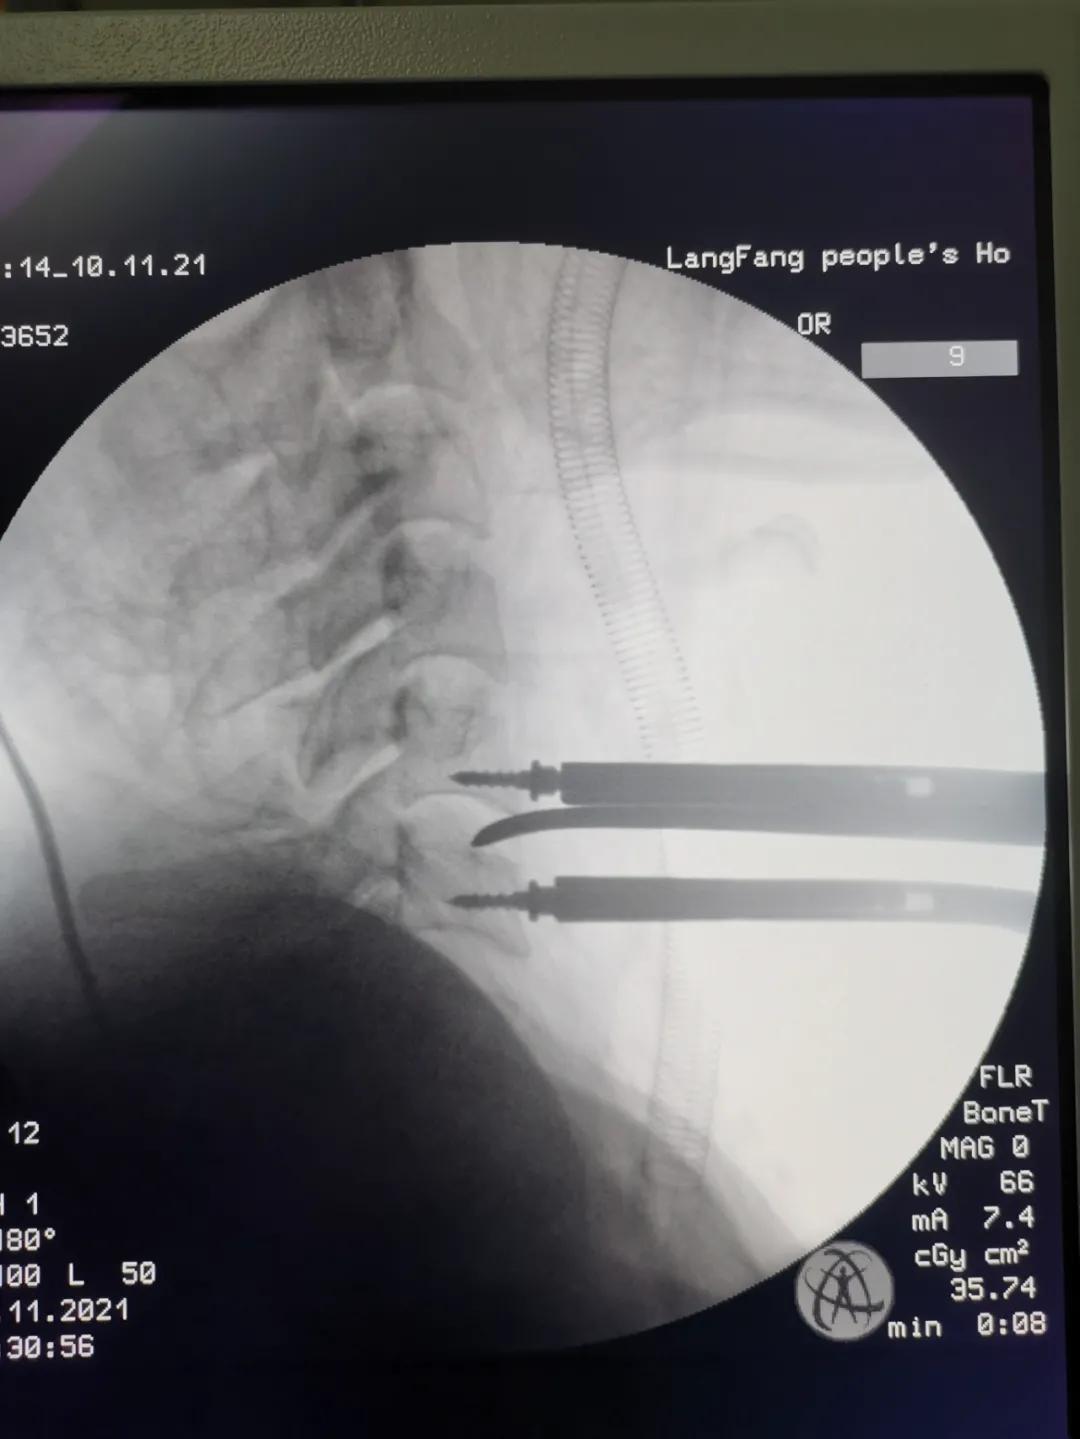

11月3日,某患者因头颈胸部外伤入院。经全面检查,诊断患者为“颈5骨折脱位,双侧关节突交锁、脊髓损伤”。患者入院后,康立星主任带领的骨一科专业团队高度重视,术前经过多次认真讨论,制定了科学周密的治疗方案。在手术麻醉科刘占波主任和马东风医生的通力配合下,康立星主任带领骨科医疗团队为患者施行“一期颈椎前后路联合骨折复位内固定术”。手术过程顺利,未输血,术中颈椎脱位完全复位,固定钢板螺钉位置良好,目前患者恢复良好。